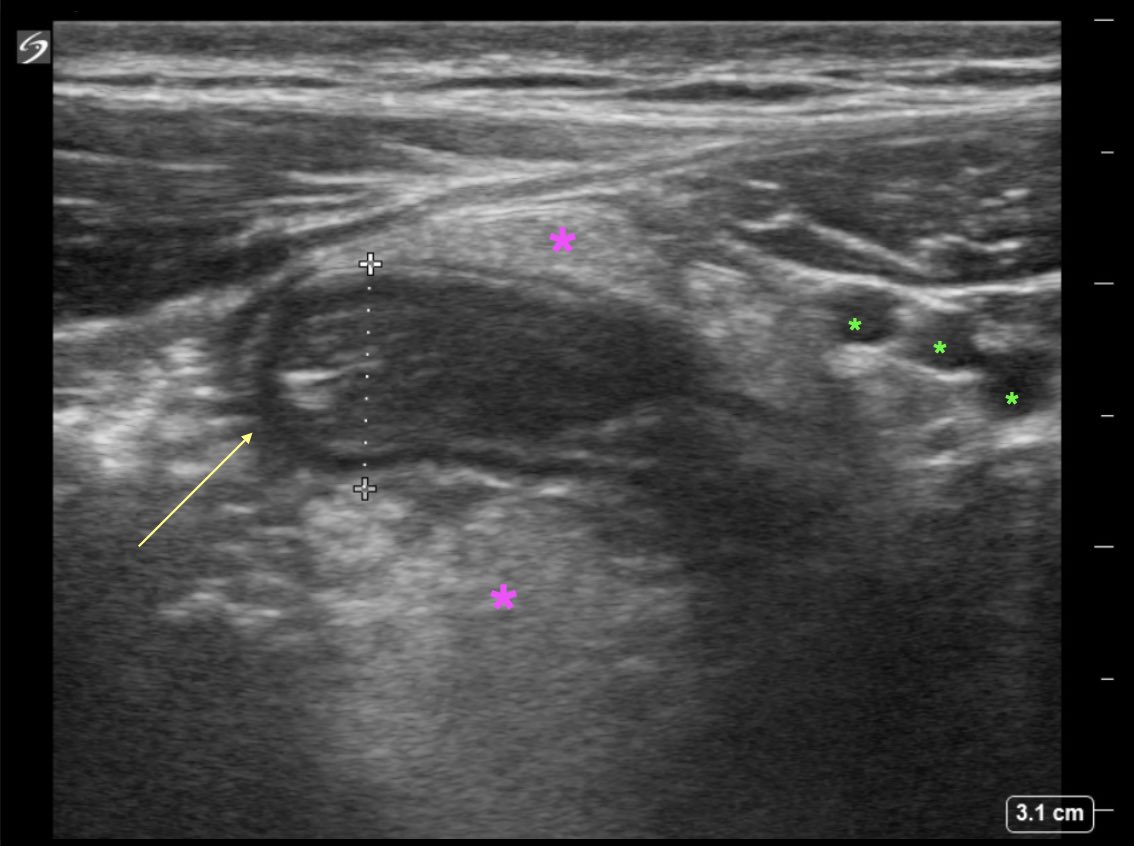

Students: What structure is represented by the yellow arrow (measuring 9mm)? Residents: What is represented by the pink stars? What structures are the green stars indicating? #raysofgray #POCUS #ultrasound #FOAMed #MedEd #emergencymedicine #medicalstudent #resident

EUSmkh's tweet image. Students: What structure is represented by the yellow arrow (measuring 9mm)?

Residents: What is represented by the pink stars? What structures are the green stars indicating?

RESOLUTION S: 9mm structure (yellow arrow)—>inflamed appendix (>6mm, non compressible, no peristalsis, blind ended) R: pink stars—>inflamed fat, green stars —>inferior epigastric vessels #raysofgray #POCUS #ultrasound #FOAMed #MedEd #emergencymedicine #medicalstudent #resident

EUSmkh's tweet image. RESOLUTION

S: 9mm structure (yellow arrow)—>inflamed appendix (>6mm, non compressible, no peristalsis, blind ended)

R: pink stars—>inflamed fat, green stars —>inferior epigastric vessels